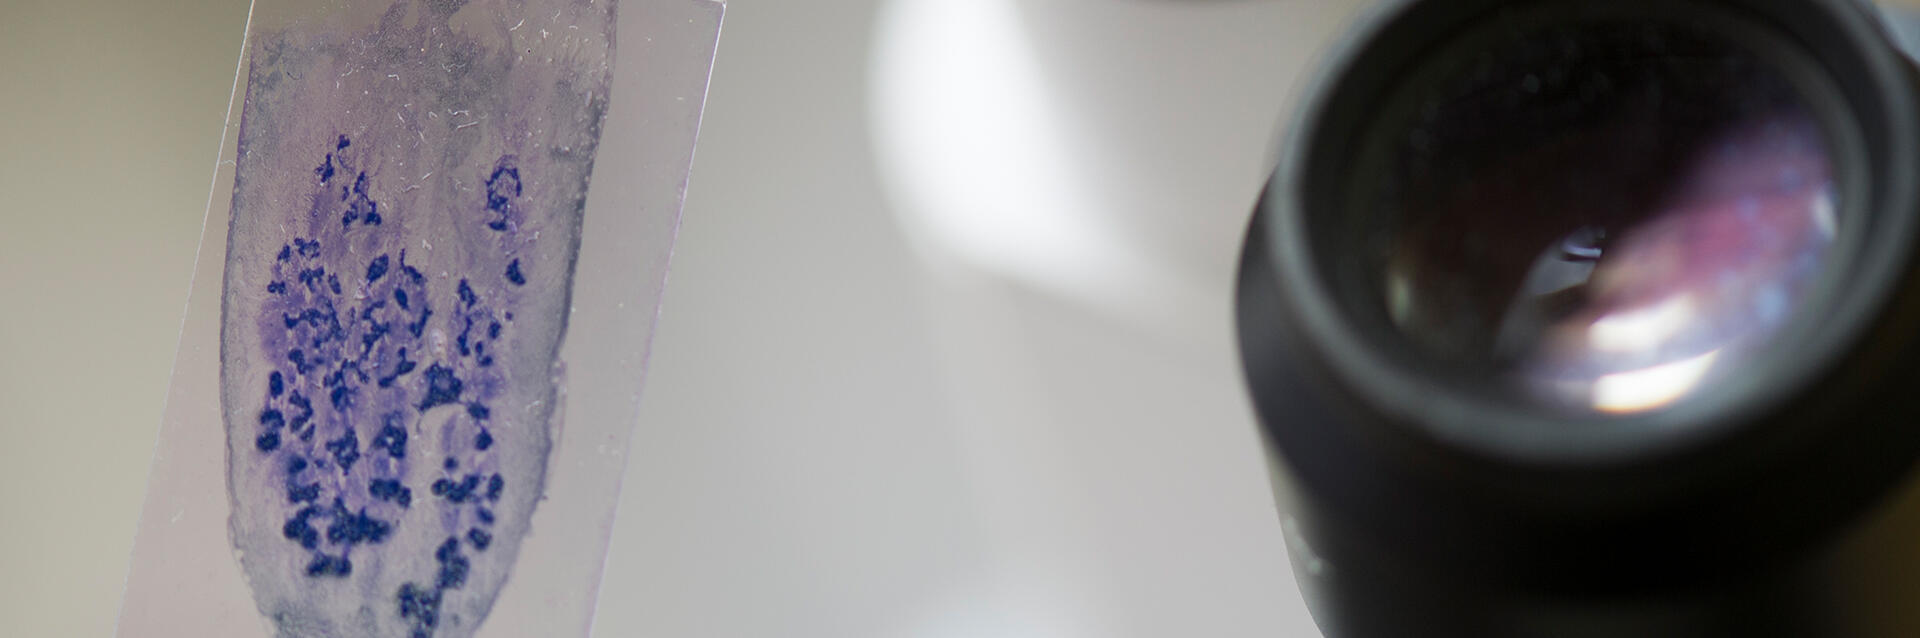

Bei einer autologen Stammzelltransplantation werden aus dem eigenen Blut des Patienten oder der Patientin Stammzellen abgefiltert, welche ihm nach einer sehr hochdosierten Chemotherapie wieder zurückgegeben werden. Dieses Therapiekonzept macht man sich häufig bei Lymphomen und dem Multiplen Myelom zunutze. Bei einer allogenen Stammzelltransplantation werden dem Patienten oder der Patientin Blutstammzellen eines anderen Menschen (beispielsweise der Geschwister, aber auch eines fremden Menschen) übertragen. Dieses Konzept kommt bei Leukämien, aber auch bei dem Multiplen Myelom zur Anwendung. Die allogene Stammzelltransplantation ist auch unter dem Schlagwort „Knochenmarktransplantation“ gemeinhin bekannt, wenngleich dieser Begriff heutzutage medizinisch nicht mehr ganz korrekt ist.